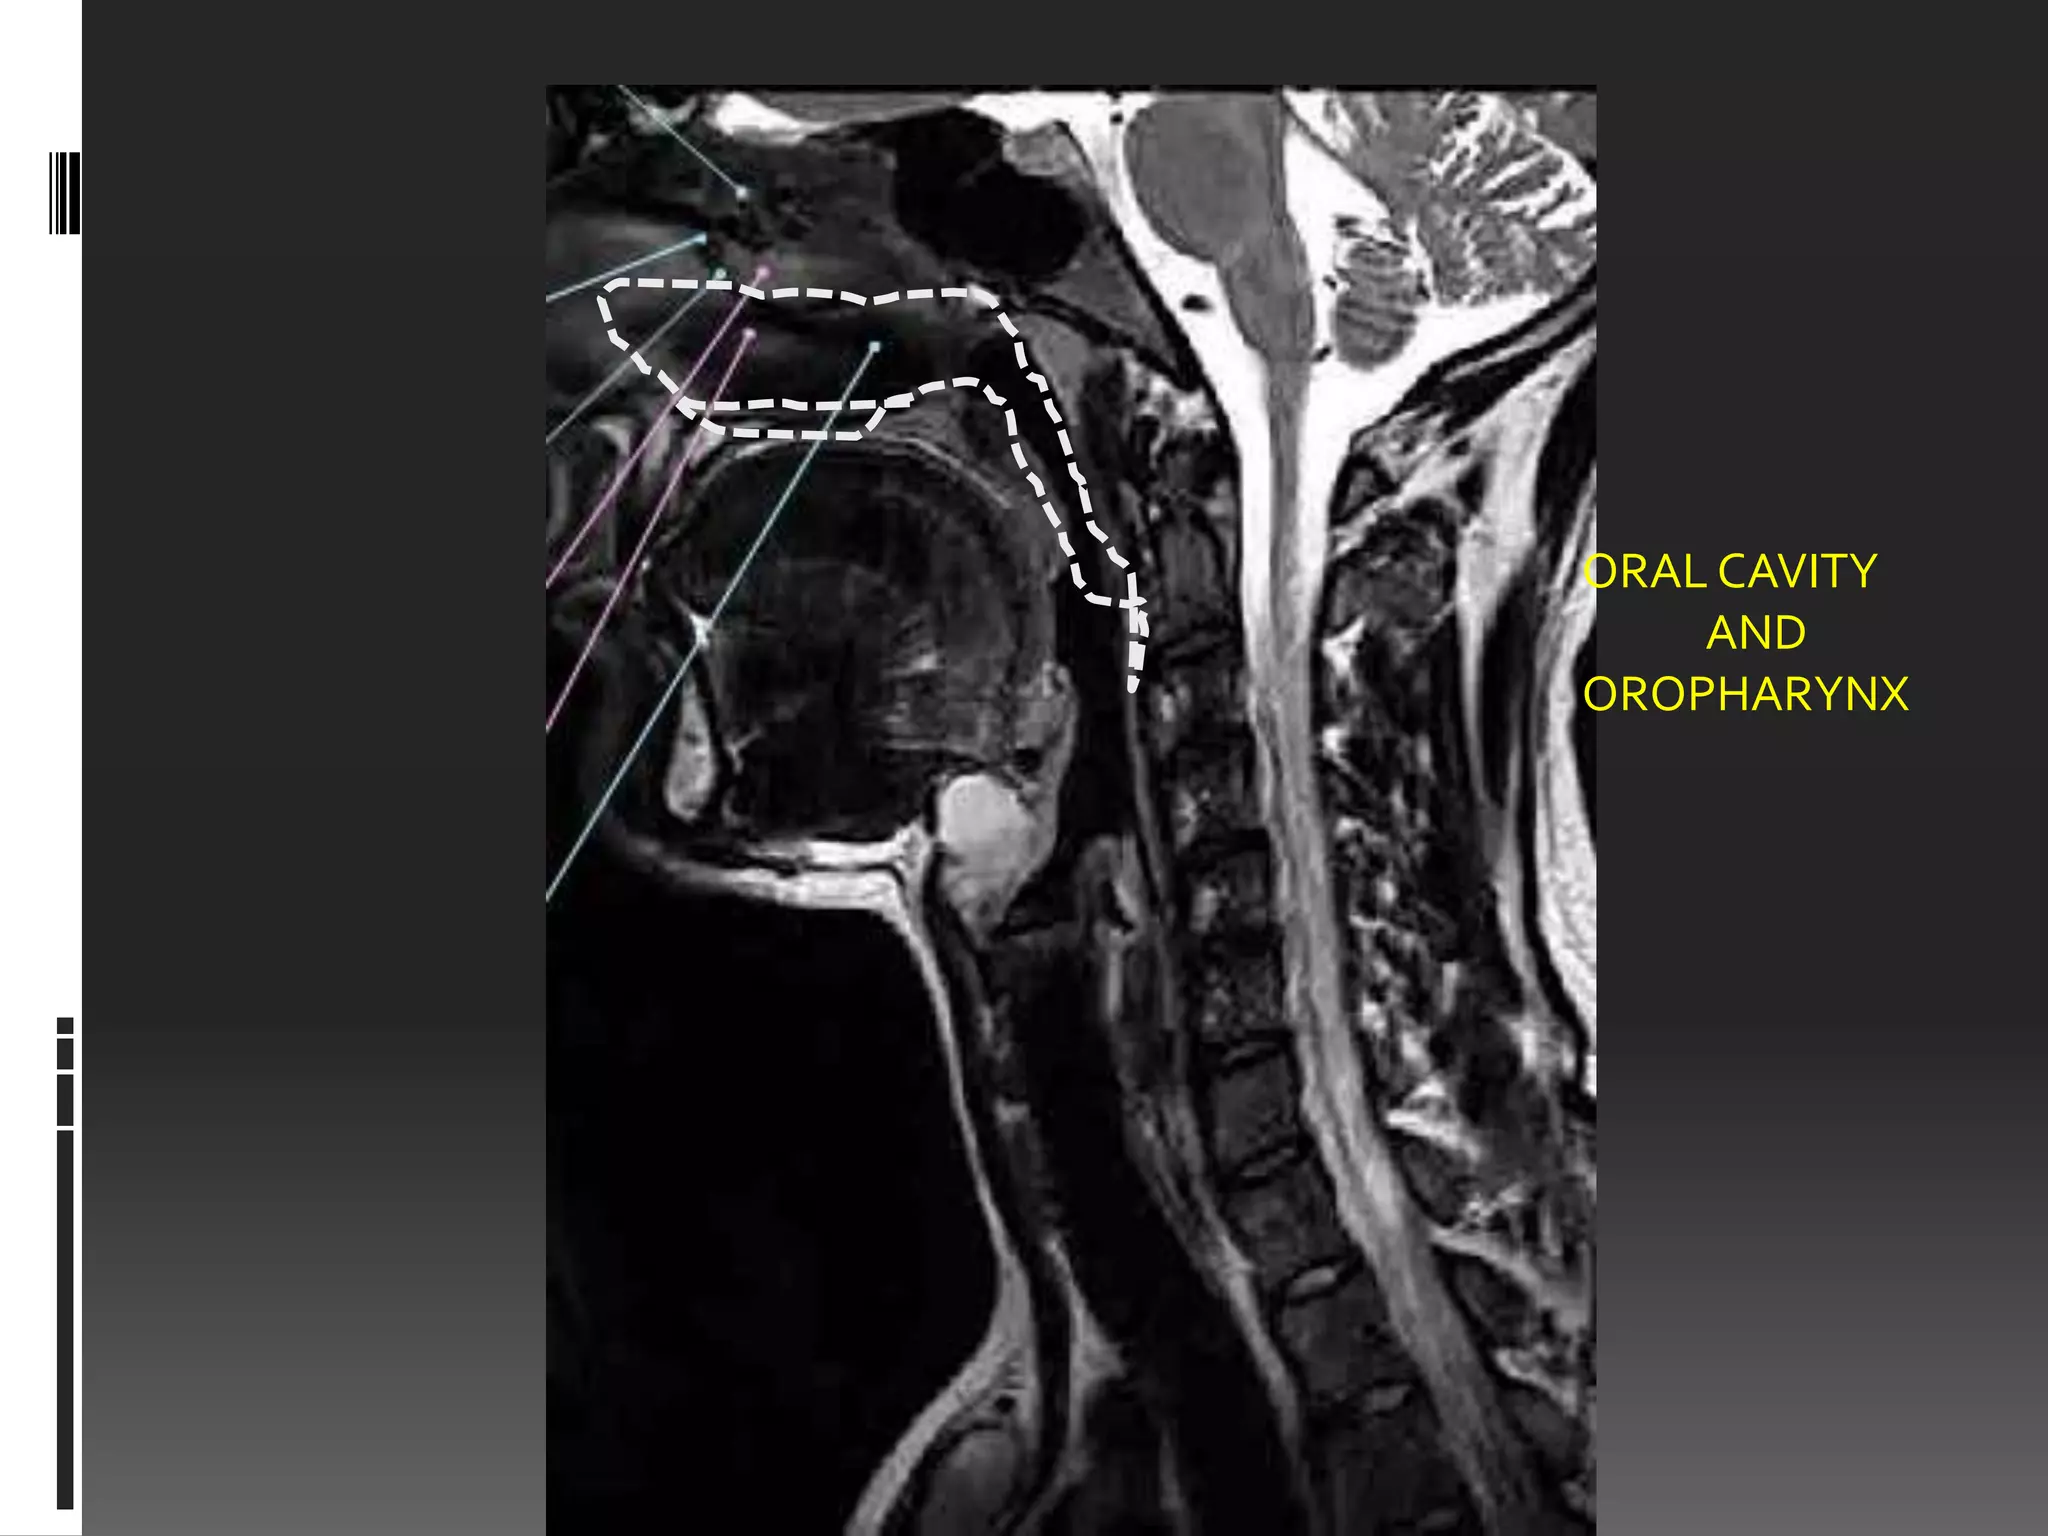

ORAL CAVITY

AND

OROPHARYNX